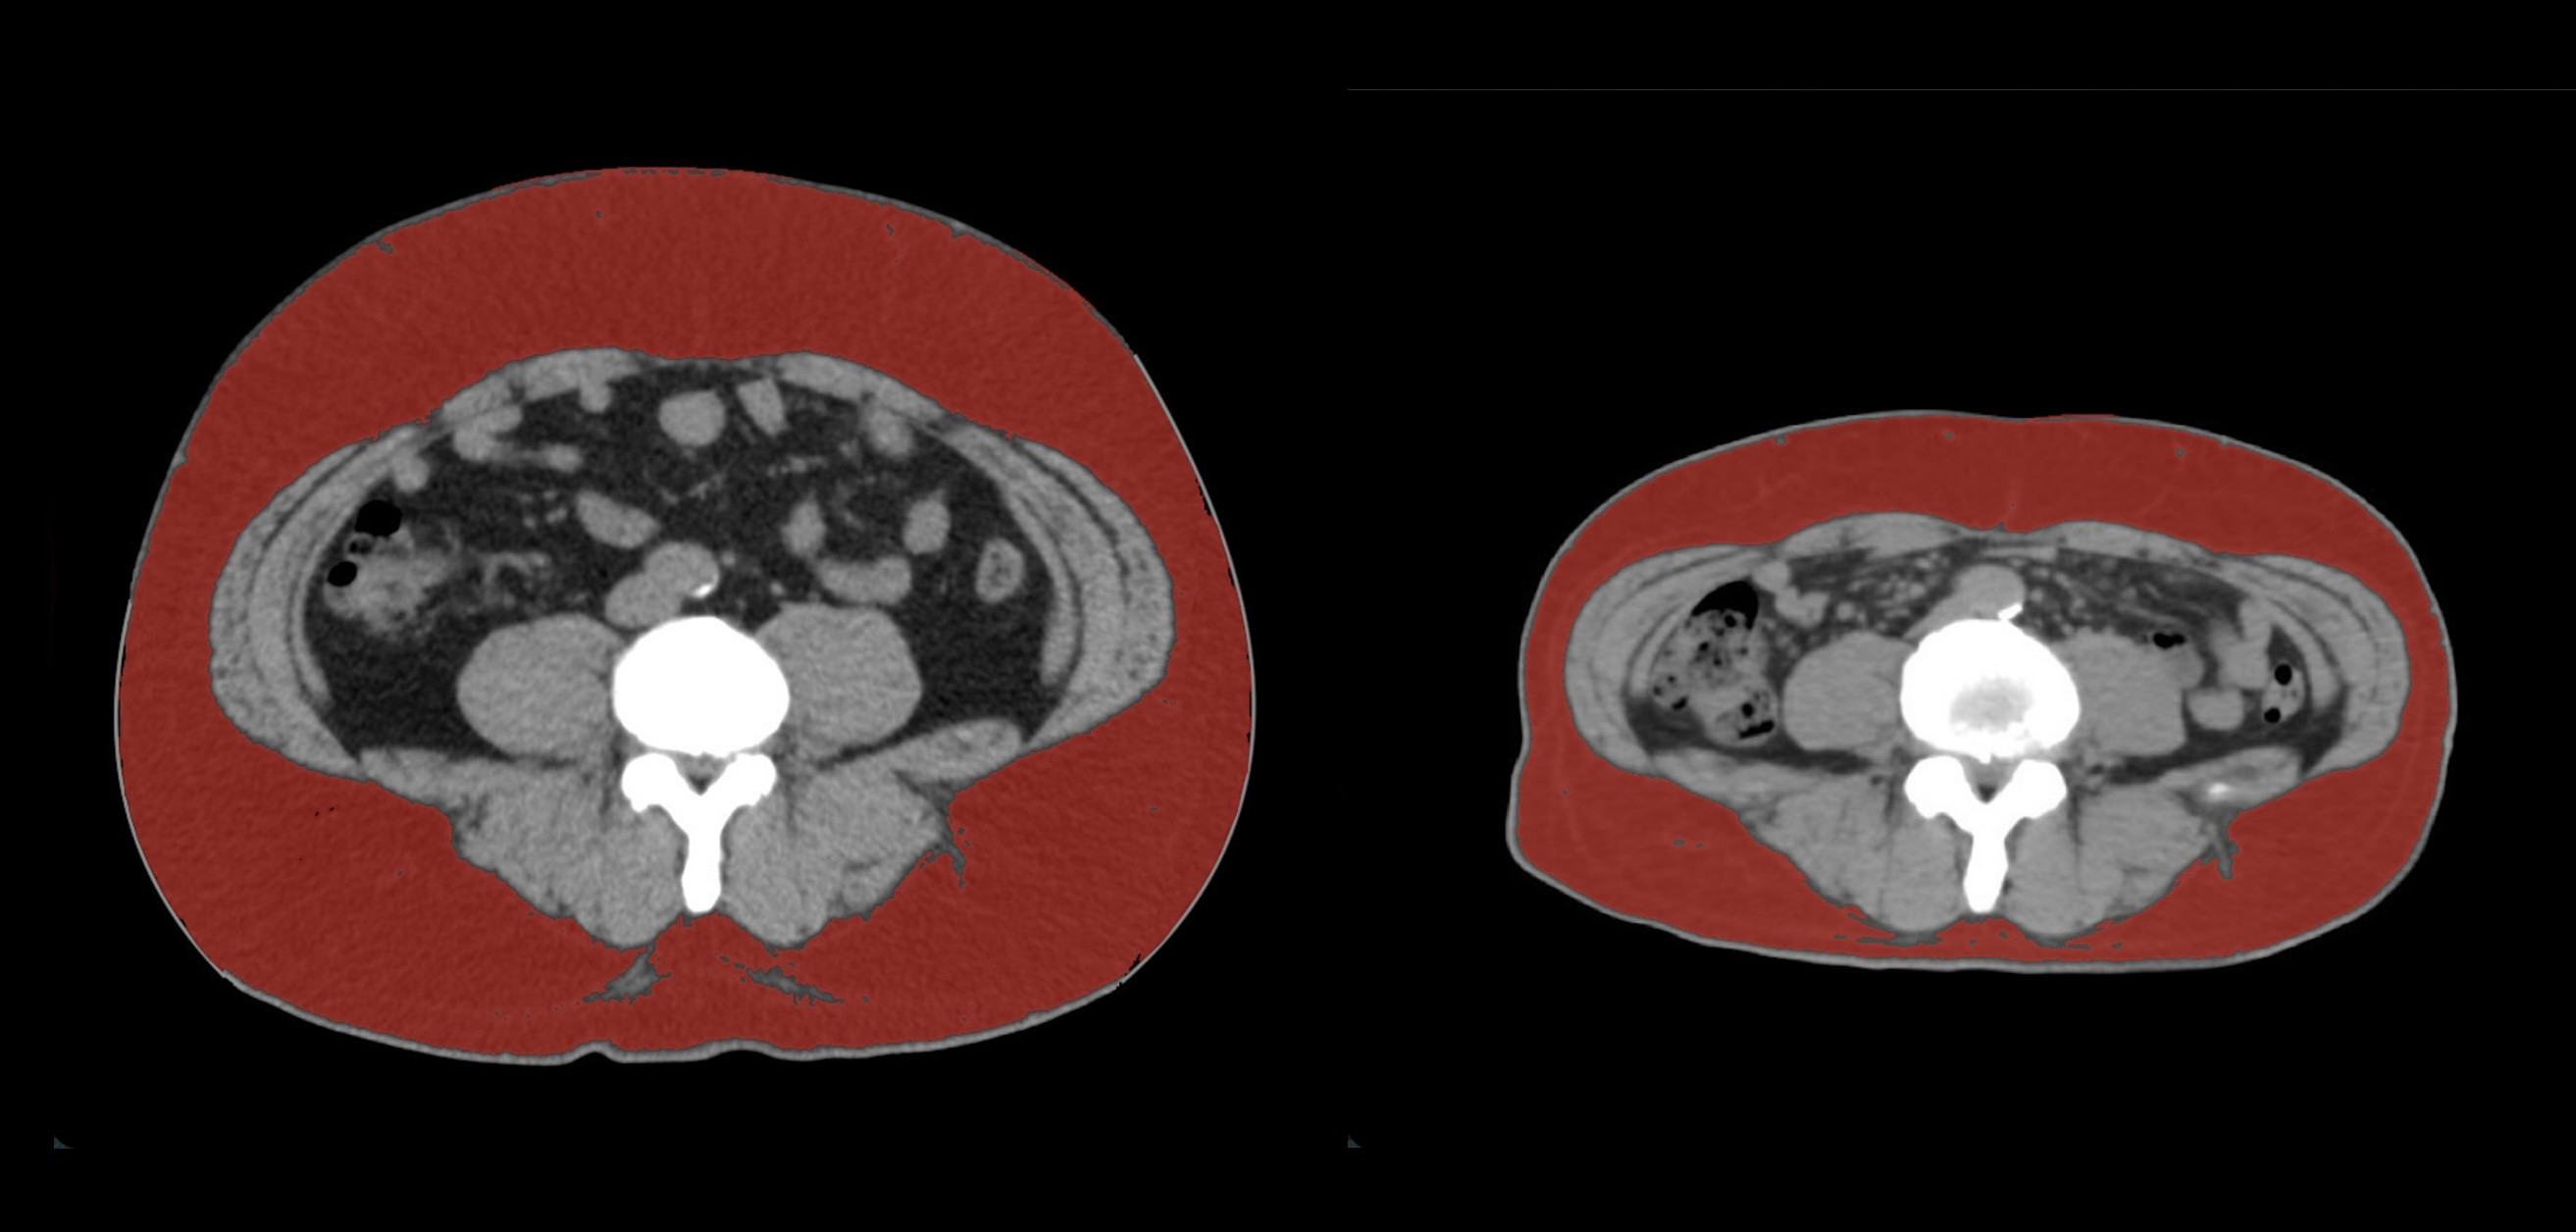

④

50代・男性(ご本人のご厚意で画像提供)

治療内容:チルゼパチド7.5mgの週1回自己注射による脂肪減少と脂肪肝改善

治療期間: 12ヶ月(52週)((用量は2.5mgから開始し最大で15mg。減量効果が得られる必要用量には個人差があります。))

費用:自由診療の場合は9900円(税込)×52(週)=514800円

想定されるリスク・副作用:下記に副作用を記載

※医療広告ガイドラインに準拠して表記

1:脂肪の減少

皮下脂肪の減少(赤色部分)